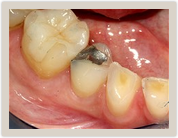

| Before Photo | After Photo |

Removal of an amalgam (silver) filling and replacement with a natural tooth colored full-ceramic filling using the CEREC system.